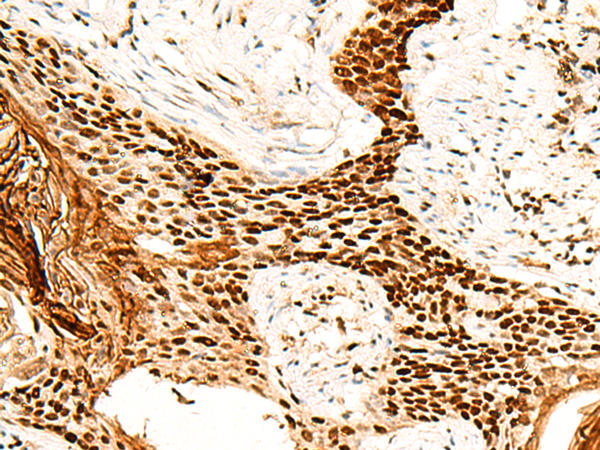

ELISA, IHC

IHC positive control:

Human esophagus cancer

IHC Recommend dilution:

40-200